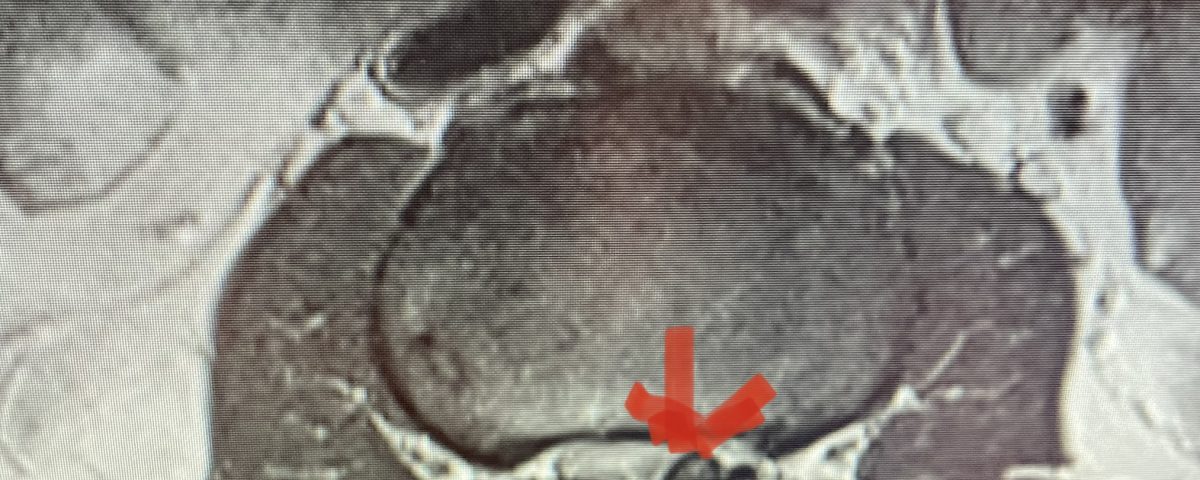

This 71 year-old male presents with a long history of progressive pain in the low back with radiation to both legs in the anterior thigh distribution, the left being worse than the right. He feels that his legs get weak. Standing and walking worsen the low back pain and lower extremity symptoms while sitting relieves the symptoms. He failed PT and epidural injections. Imaging studies revealed severe lateral recess stenosis do mainly to severed thickened ligament. He had severe lateral recess stenosis from L2-5 (Fig 4) as well as central stenosis. He also had a slight retrolisthesis at L3-4 and L4-5. He had on the left in particular a very enlarged protruded segment of thickened ligamentum in the subarticular recess at L3-4 (Fig 5) which was likely responsible for his left leg pain as the patient had symptoms of an L4-type syndrome. It was decided to perform a decompressive laminectomy from L2-5. Because of retrolisthesis it was decided to perform a noninstrumented onlay bone fusion or an in situ fusion from L3-5. In this case it was very important to decompress not only the thecal sac, but also the lateral recess with the thickened ligament at the point where the nerve makes its course into the forman. As a surgeon you must really undercut the facet joints to clear the lateral recess and feel how the nerve root with one’s instrument is being released as it enters the foramen. Postoperatively the patient had resolution of his leg pain, particularly on the left. In this case the most significant pathology was in the left L3-4 lateral recess, his symptoms and MRI findings correlated well which leads to the most successful operations.

Figure 5: Axial T2-weighted MRI demonstrating severe bilateral lateral recess stenosis secondary to thickened ligamentum flavum. Notice the prominence of the left ligamentum in the subarticular recess.